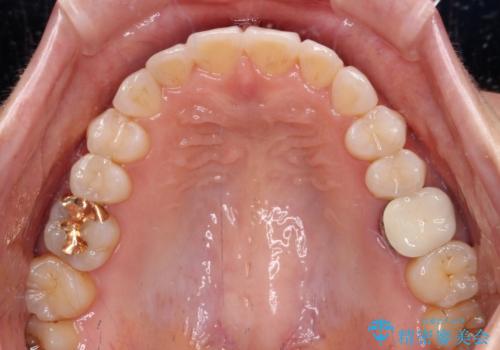

- 前歯のデコボコと上下スペースと前歯の隙間を気にして来院された患者様です。

目立たない装置を希望とのことでインビザラインにより、デコボコを解消しつつ、上下の前歯の隙間を閉じていくこととしました。

デコボコはあっという間に解消されましたが、上下前歯の隙間がなかなか解消されませんでした。

飲み込みの際に舌を前方に突出する癖があり、飲み込みの度に前歯に強く接触していたため、上下前歯の隙間が維持されていました。

舌の訓練を徹底していただいたことで、徐々に隙間は解消され、きれいな歯列に整えることができました。